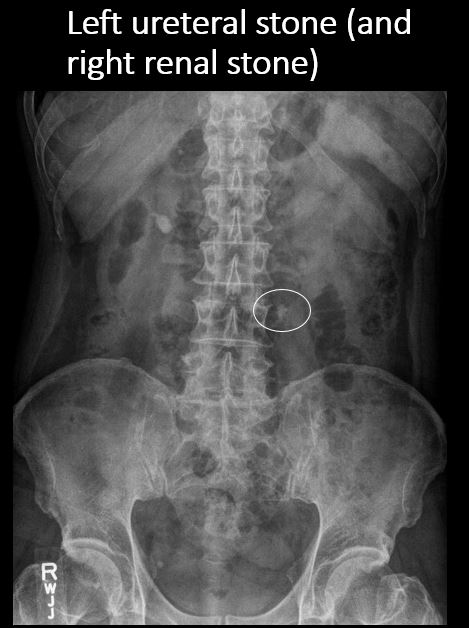

There are renal associated calcifications. [Yes/No]

There is a right or left ureteral calcification/stone anywhere from the renal pelvis to the UVJ. [Yes/No]